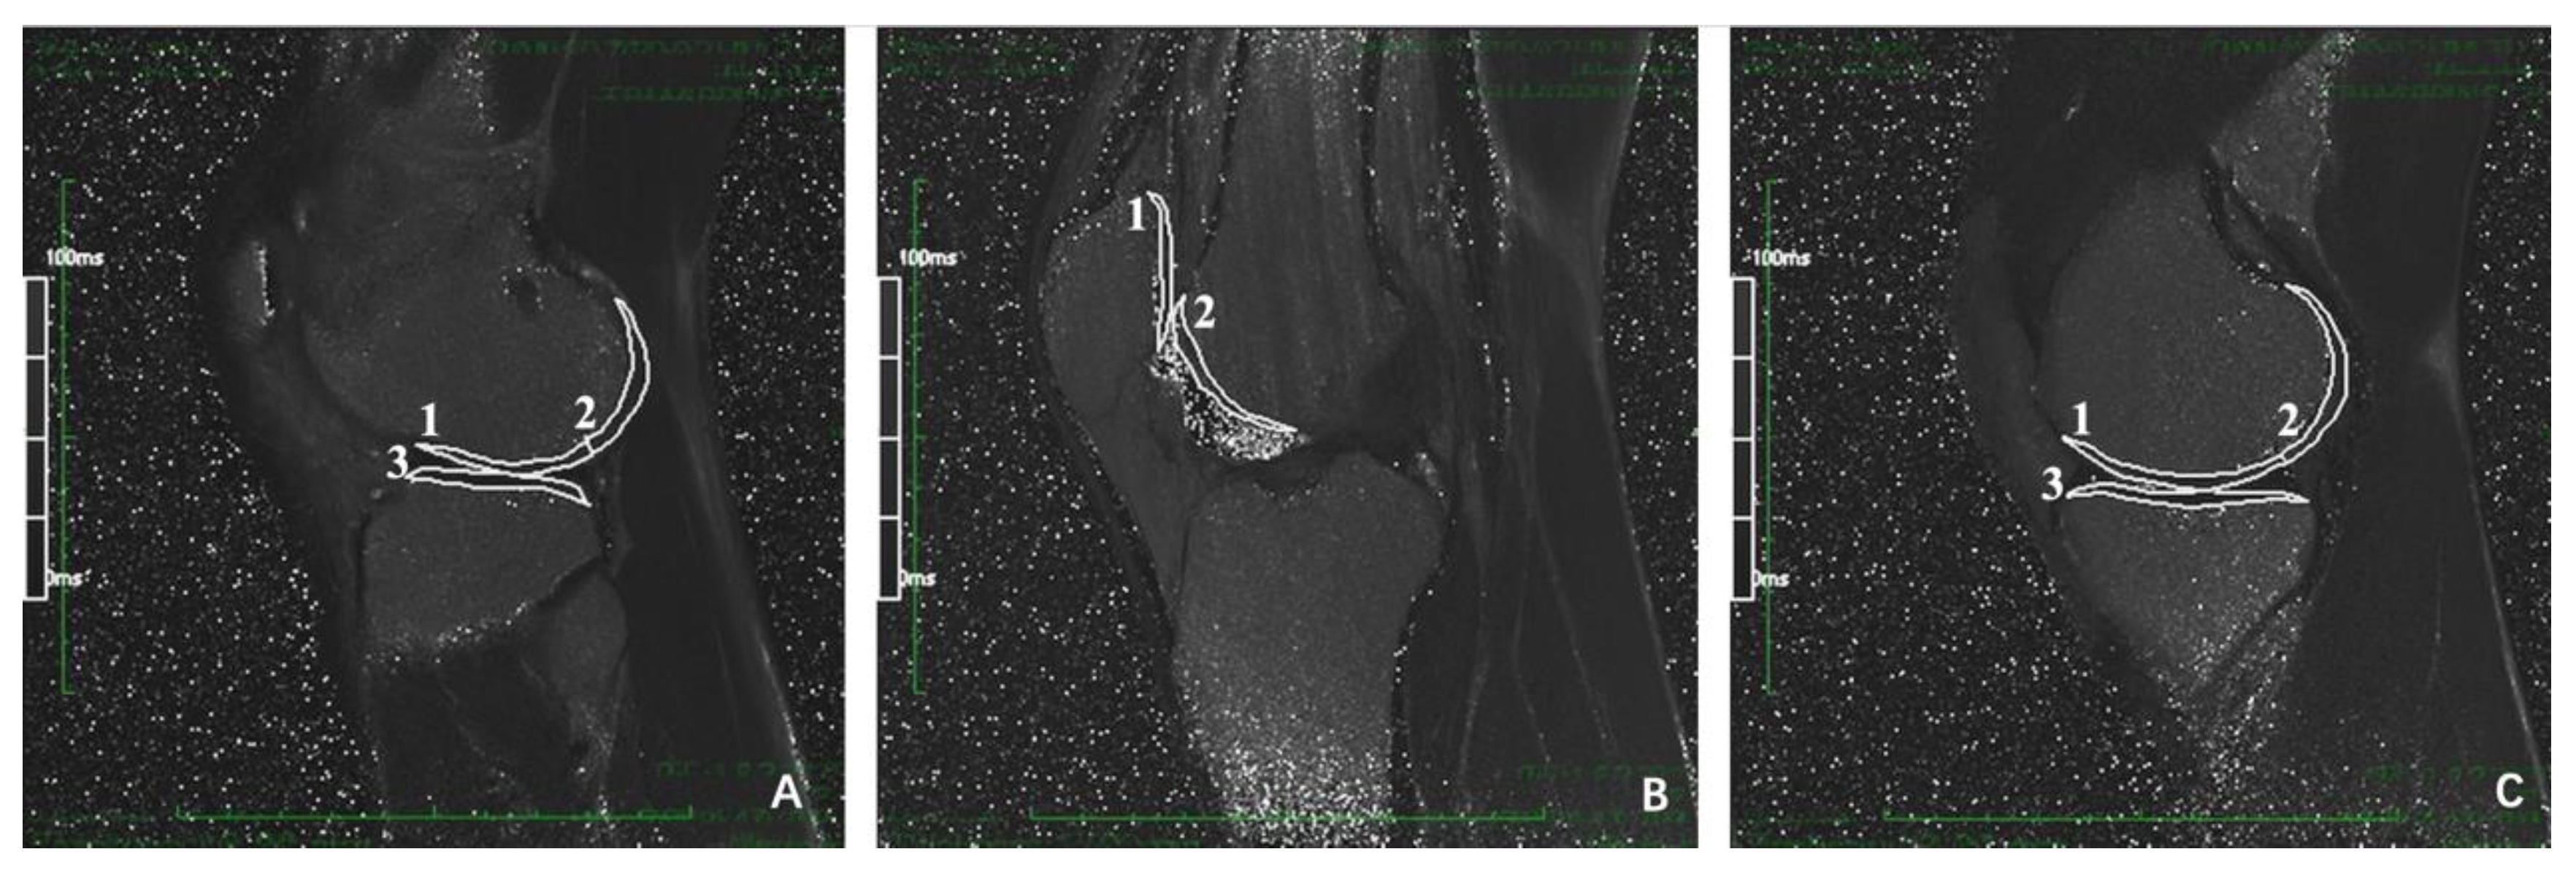

The T2 mapping color scale of articular cartilage in HT-PTI group and FHT group at 6, 12, 24 and 60 months after operation is shown in Figure 5 and Figure 6. If the false color of cartilage is close to red, the cartilage had higher T2 value and more damage. Meanwhile, if the color is closer to dark blue, the cartilage had lower T2 value and less damage.

Figure 5.

Sagittal T2 mapping of knee joint in HT-PTI group. (A-1–A-3) show the lateral tibiofemoral joint, patellofemoral joint and medial tibiofemoral joint in HT-PTI group at 6 months after operation; (B-1–B-3) show the lateral tibiofemoral joint, patellofemoral joint and medial tibiofemoral joint in HT-PTI group 12 months after operation; (C-1–C-3) show the lateral tibiofemoral joint, patellofemoral joint and medial tibiofemoral joint in HT-PTI group 24 months after operation; (D-1–D-3) show the lateral tibiofemoral joint, patellofemoral joint and medial tibiofemoral joint in HT-PTI group 60 months after operation.

Figure 6.

T2 mapping of knee joint sagittal plane in FHT group. (A-1–A-3) show the lateral tibiofemoral joint, patellofemoral joint and medial tibiofemoral joint at 6 months after operation in FHT group; (B-1–B-3) show the lateral tibiofemoral joint, patellofemoral joint and medial tibiofemoral joint 12 months after operation in FHT group; (C-1–C-3) show the lateral tibiofemoral joint, patellofemoral joint and medial tibiofemoral joint 24 months after operation in FHT group; (D-1–D-3) show the lateral tibiofemoral joint, patellofemoral joint and medial tibiofemoral joint in FHT group 60 months after operation.

As shown in Figure 7, the preoperative cartilage T2 values had no significant difference in each sub-region of knee joint between groups (p > 0.05). Compared with HT-PTI group, the FHT group had higher T2 values in P, TrF, pMFC, MT and LT at 6th month, in aLFC, aMFC, MT and LT at 12 months, in TrF, aLFC, aMFC, LT and MT at 24 months, and in TrF, aLFC, aMFC, LT and MT at 60 months (all p < 0.05).